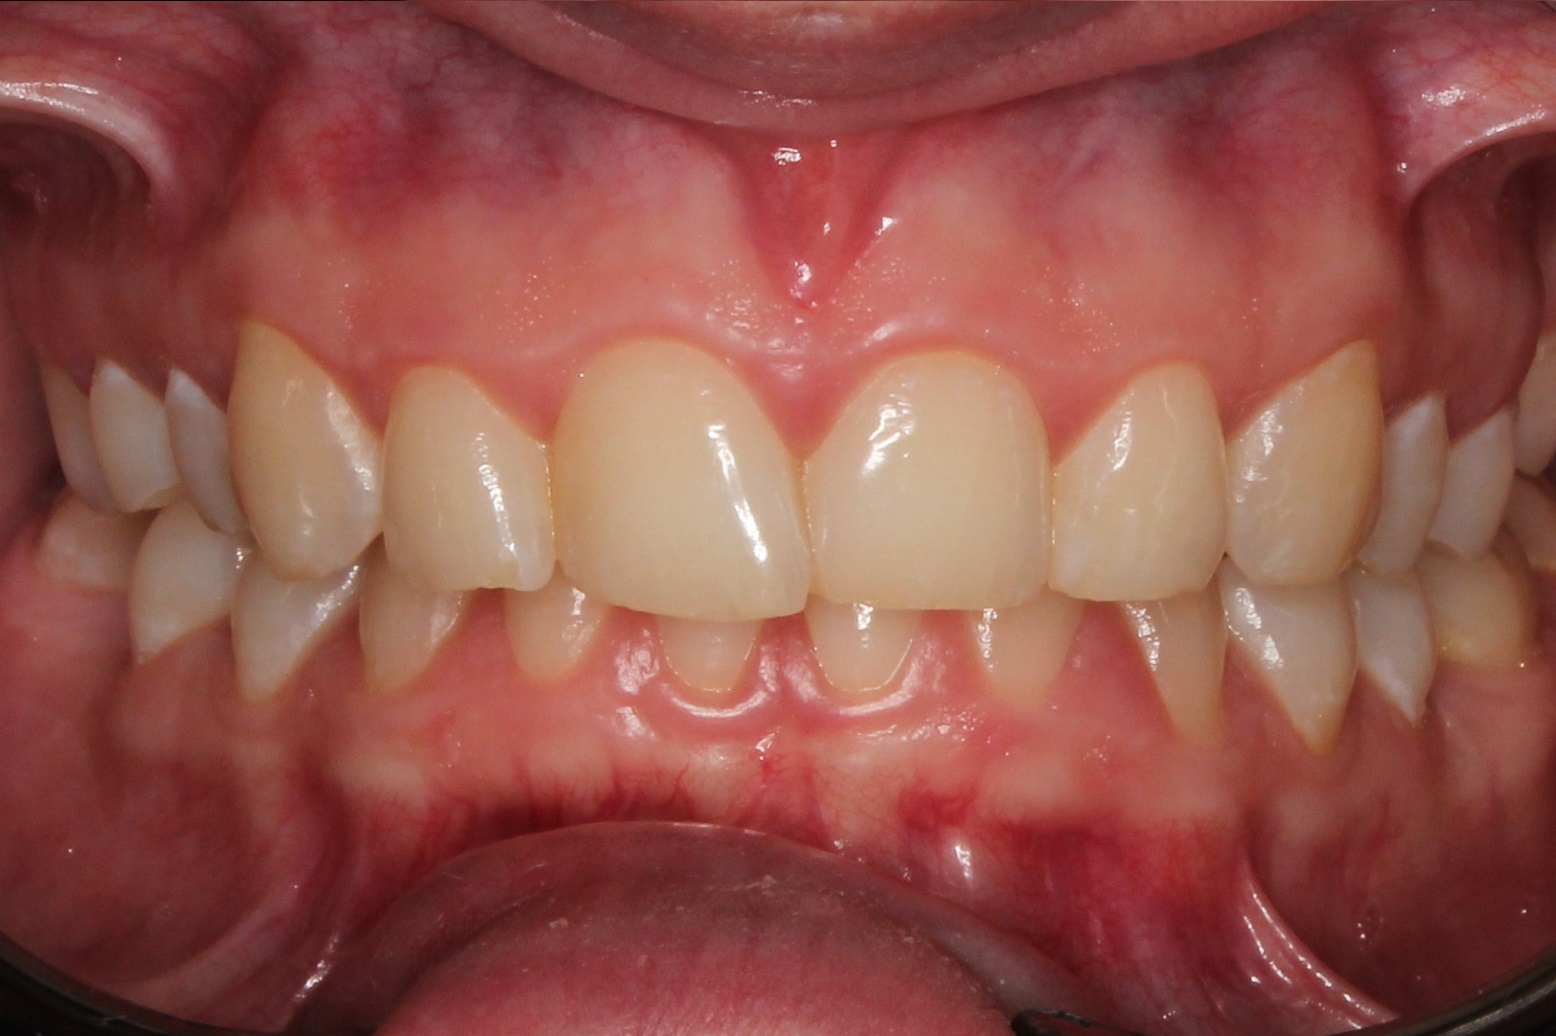

До и После: Лечение глубокого прикуса элайнерами

Лечение глубокого прикуса элайнерами. Начало лечения. Фиксация элайнеров